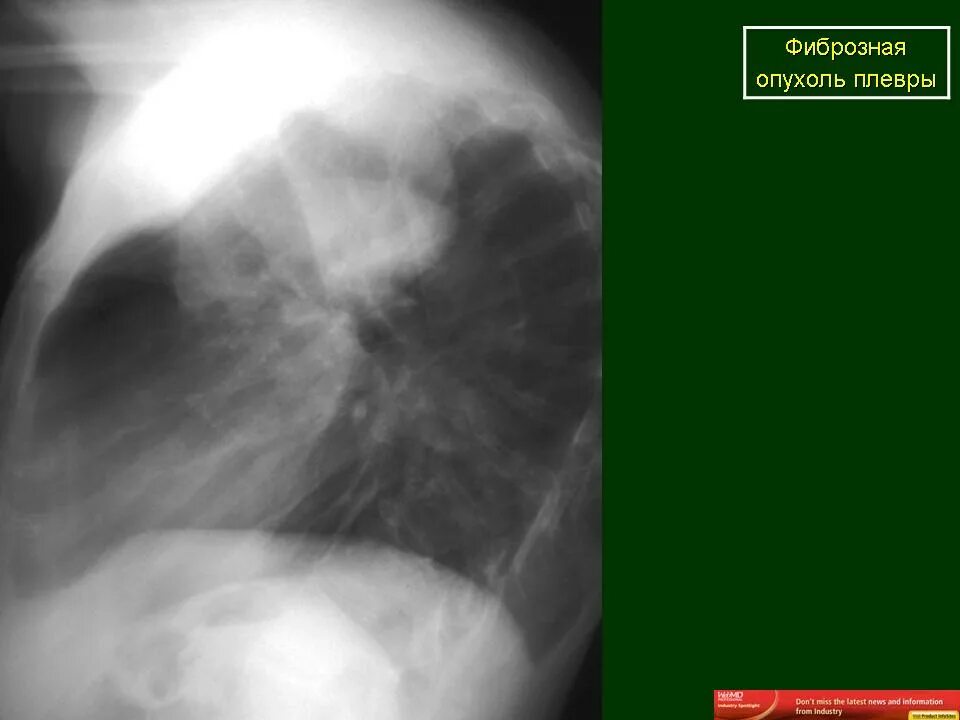

Метастазы плевры